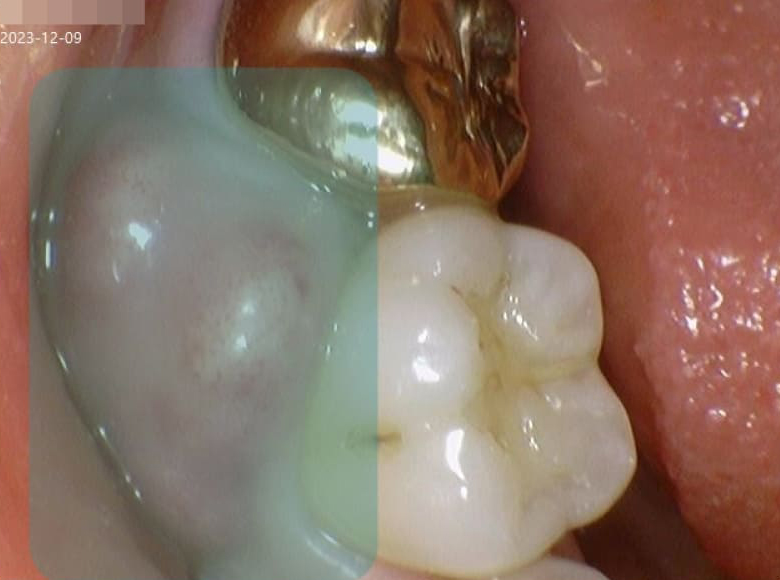

잇몸수술 전후 사진

VS

• Before

중증도의 치주염으로 인해 봉와직염 상태에 이를 정도로 많이 붓고 농이 나오는 상태의 우측 하단의 어금니 부위에 대해 잇몸 수술을 진행했습니다.

• After

잇몸수술 후 2주가 지나 통증과 붓기가 완전히 사라진 것을 확인할 수 있습니다.